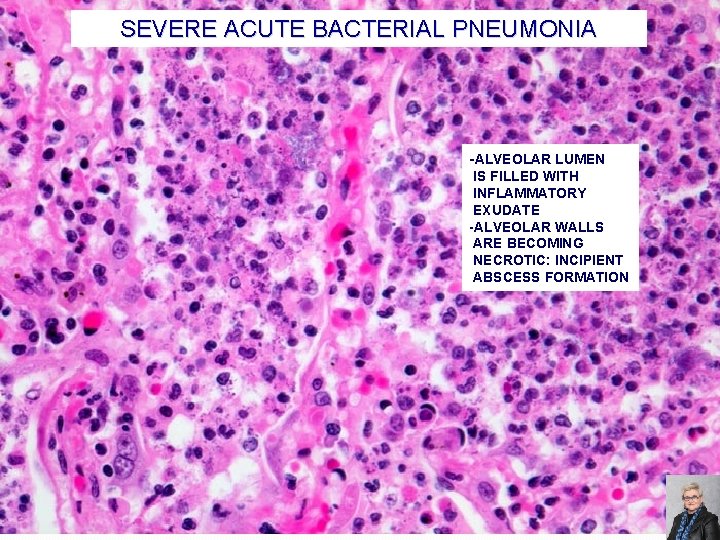

SEVERE ACUTE BACTERIAL PNEUMONIA PMNs EDEMATOUS, HYPEREMIC ALVEOLAR WALL EDEMA 72

SEVERE ACUTE BACTERIAL PNEUMONIA -ALVEOLAR LUMEN IS FILLED WITH INFLAMMATORY EXUDATE -ALVEOLAR WALLS ARE BECOMING NECROTIC: INCIPIENT ABSCESS FORMATION 73